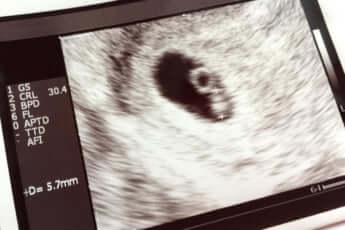

NIPT実施施設数の推移。NIPTをビジネスチャンスと捉えた企業などが次々に参入し、全国の診療所に「クリニック売上向上のご提案」といった資料を送って勧誘した。採血をするだけの美容皮膚科や内科のクリニックが一気に増え、無認証施設の数は瞬く間に認証施設を追い越した (画像は『出生前検査を考えたら読む本』より)